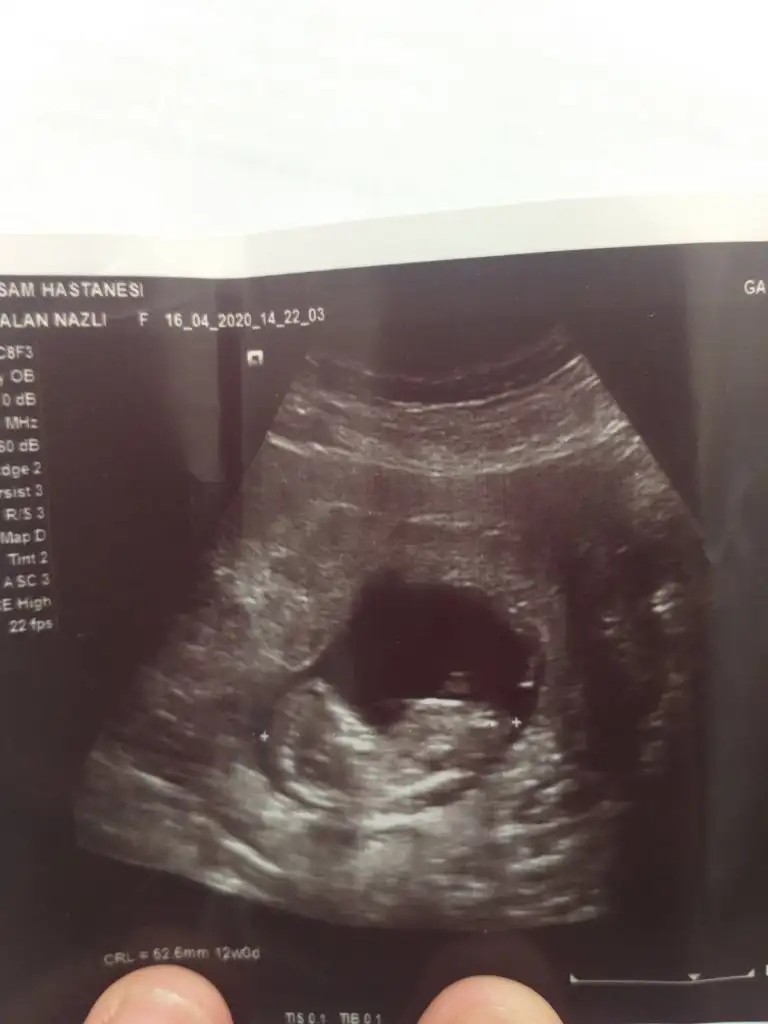

Merhabalar bana da tahminde bulunur musunuz rica etsem 11 haftalık teşekkürler şimdidenBuraya paylaşın mesaj yazdıgınızın hemen sol altta dosya ekleye tıklayın![]()

Şimdilik kız gibi sanki 12-13 haftasınıda paylaşın

Kime yazdınız alıntı yapın yada cevaplaya tıklayın kime yazacaksanız sorunun altında cvpla varKız gibi duruyorallah hayırlı saglıklı bi şekilde kucagınıza almayı nasip etsin

%30 erkek ola bilir

Tamamdır çok teşekkürlerŞimdilik kız gibi sanki 12-13 haftasınıda paylaşın